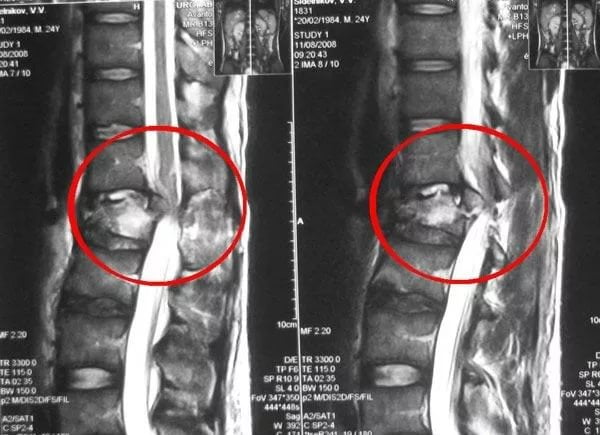

| 2 степень | Усиление болезненности, которая начинает отдавать в нижнюю зону ноги. С каждым месяцем происходит нарушение работы сочленения, развивается хромота, появляется характерный хруст при ходьбе. Возможно укорочение конечности из-за перекоса в тазовых костях. На снимках четко прослеживается смещение головки сустава вверх |

| 3 степень | Развитие постоянной болезненности, которая беспокоит человека даже ночью. Специфическая кривая походка. Выраженное нарушение движений, спазмообразные боли при начале ходьбы. При выполнении рентгена видно, как головка сустава сильно поражена. На ней локализовано множество дефектов |